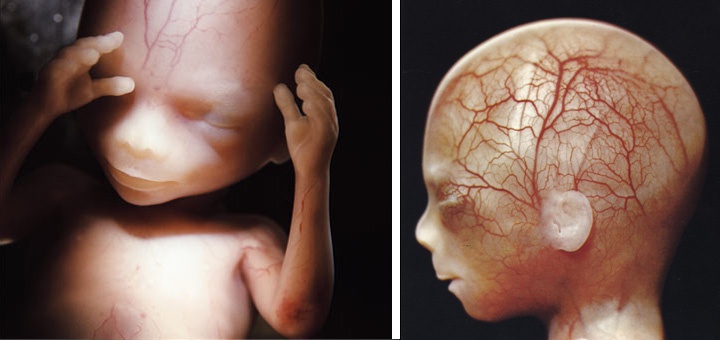

16-17 недель беременности: развитие малыша